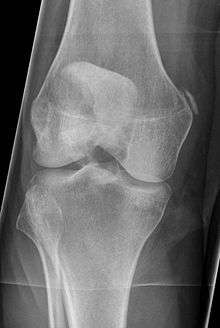

Pellegrini-Stieda syndrome. Also visible is a fracture of the patella.

Pellegrine–Stieda syndrome (also called Stieda disease and Köhler–Pellegrine–Stieda disease) refers to the ossification of the superior part of the medial collateral ligament of the knee. It is a common incidental finding on knee radiographs. It is named for the Italian surgeon A. Pellegrini (b. 1877) and the German surgeon A. Stieda (1869–1945).[1]